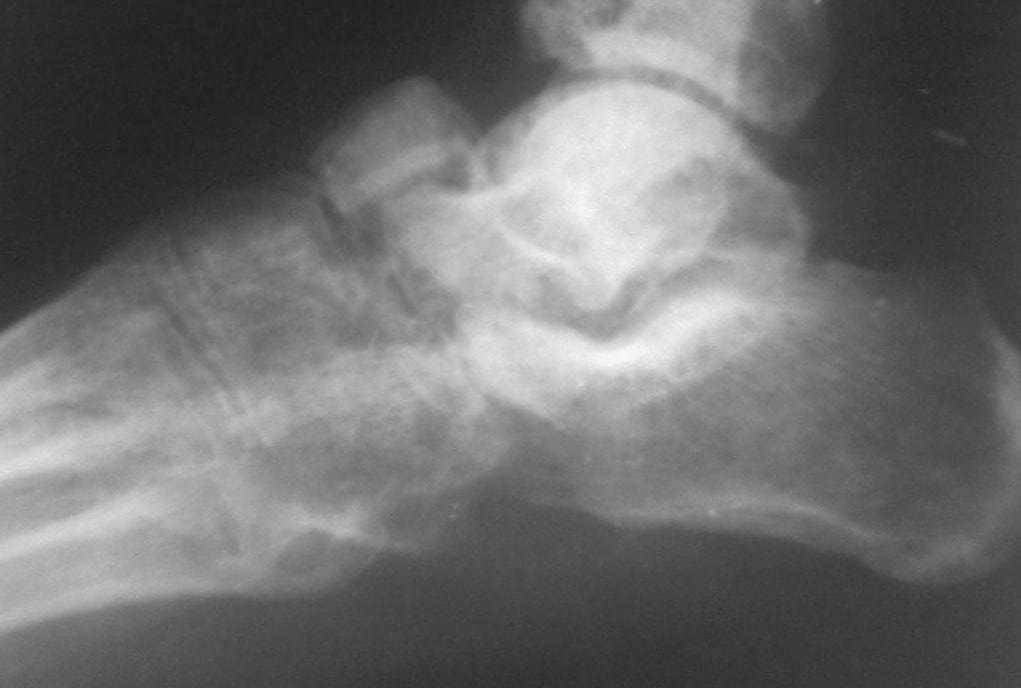

Обратился  больной  46 лет. 3 месяца  назад  получил  травму  левой

стопы в  результате  ДТП, живет в  отдаленный  степной  зоне, лечился

у  местного  табиба. Ходит при  помощи двух  костылей, наступая на

пятку, на  передний  отд.  стопы  наступать  не  может  из-за боли,

умеренная  отечность  стопы и  деформация в  обл ладьевидной кости,

движения  в  голеностопном суставе в  польном  обьеме, в среднем

отд.  ограничены  и  болезненны.